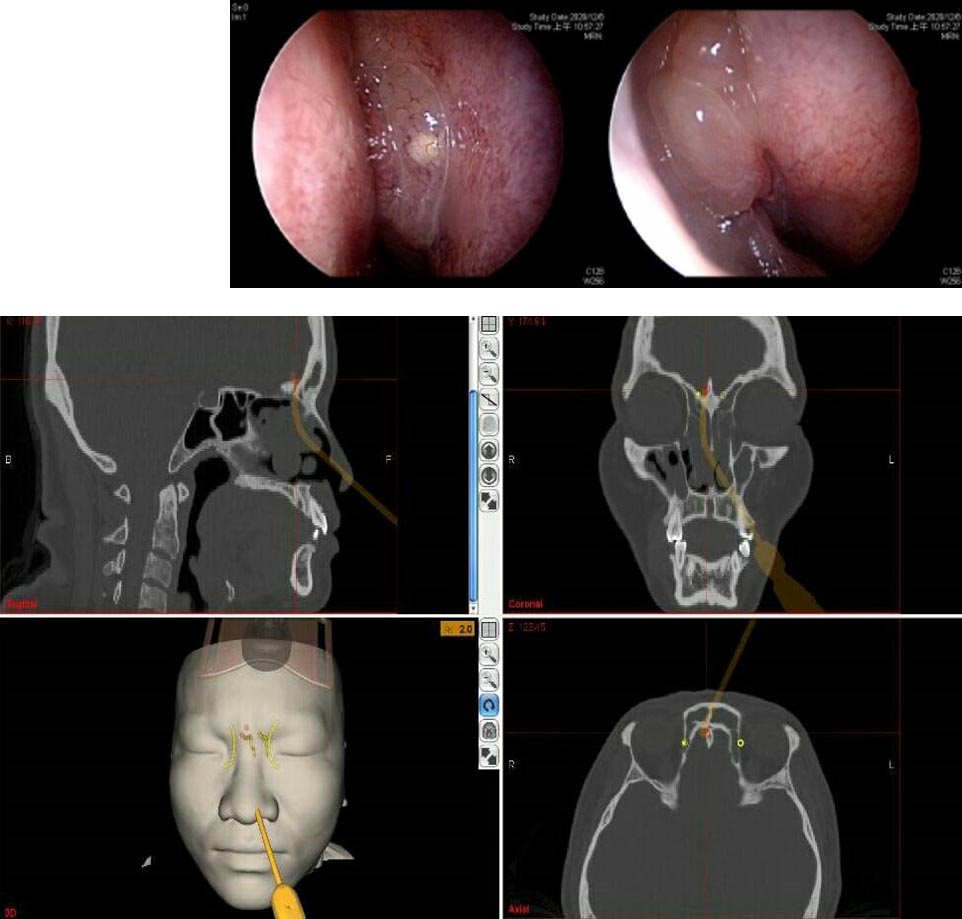

「内視鏡下鼻副鼻腔・頭蓋底手術[3DCT画像データDVD-ROM付] CT読影と基本手技」伊藤 壽一定価: ¥ 12000#伊藤壽一 #伊藤_壽一 #本 #自然/医療・薬学・健康裁断済みです。表紙には写真のような劣化があります。下側面には赤いマーカーがひいてある部分があります。裁断済みのため状態は全体的に悪いとさせて頂いております。中古品、素人検品、自宅保管にご理解頂きご購入お願い致します。佐川急便/日本郵便に変更になる場合もあります。